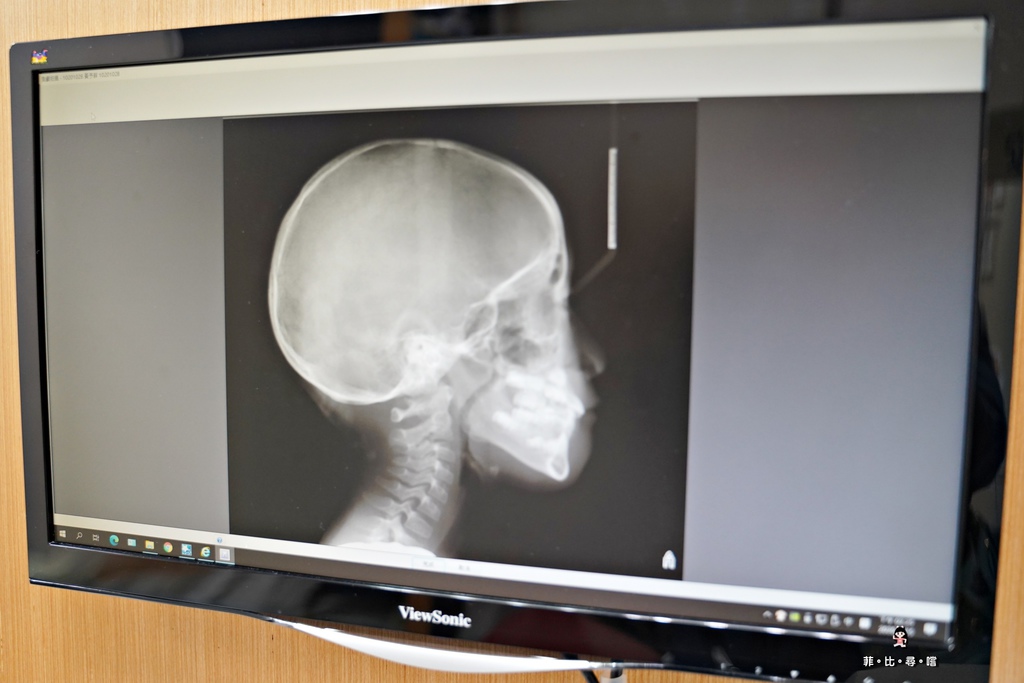

還有拍攝口腔X光片

小朋友骨骼的發育趨勢,也是評估矯正療程時要列入考量的因素之一

邱醫師針對口腔掃描後的影像來作評估

小菲菲除了有齒列不正之外

不知道和她因鼻子過敏都張口睡覺有沒有關係

還有「牙弓狹窄」的問題

導致"2“的位置,在乳牙掉落後,因為沒有空間,所以新牙一直沒有長出來!